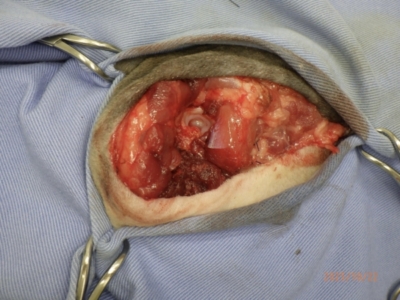

筋肉の断端や股関節部を包める様に皮膚を余らせる様に切開。

太い動脈や神経を丁寧に剥離、結紮しながら行います。

筋肉を切断し、指差しているところが大腿骨の骨頭部分です。

足を離した後。